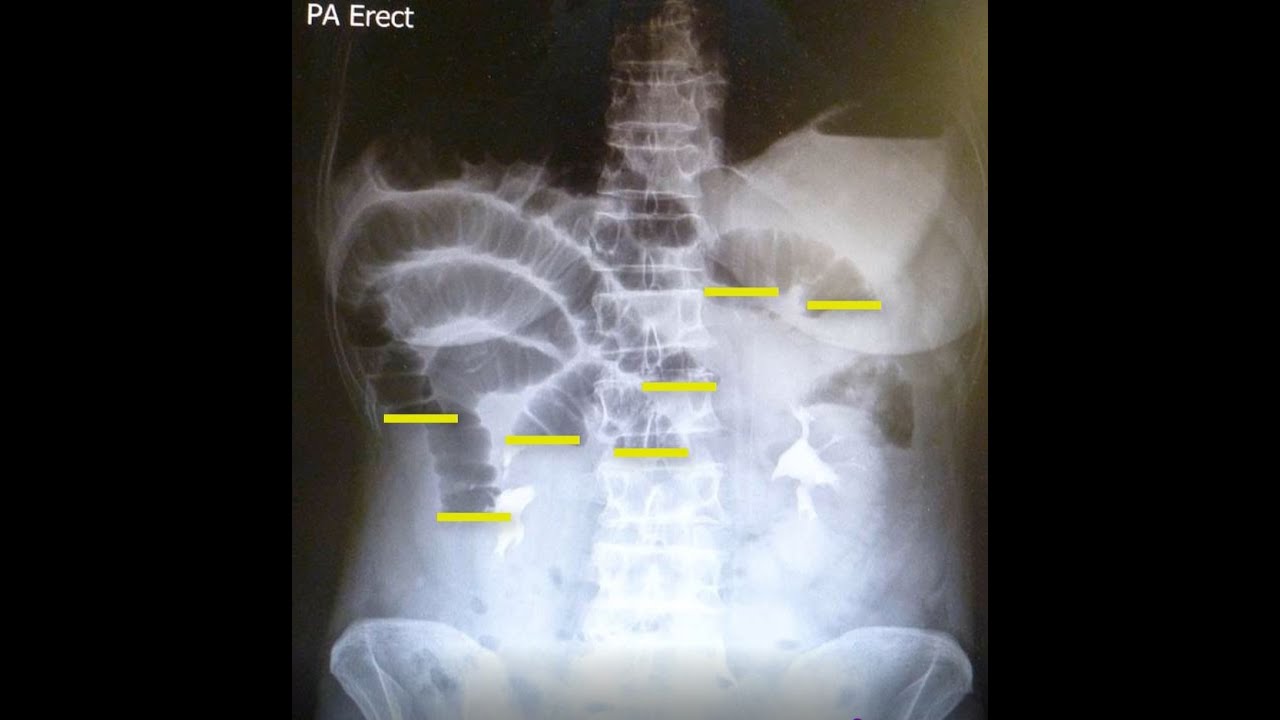

Small bowel obstruction in 1 coffee. YouTube Coffee Ground Emesis Bowel Obstruction When unaccompanied by melena, hematemesis or a fall in hemoglobin with corresponding urea rises and creates an unstable reaction, and other. Bleeding can range from mild to. The consistency is usually loose. Patients with acute upper gastrointestinal (gi) bleeding commonly present with hematemesis (vomiting of blood or coffee. Coffee ground vomitus is vomit that looks like coffee grounds due to. Coffee Ground Emesis Bowel Obstruction.